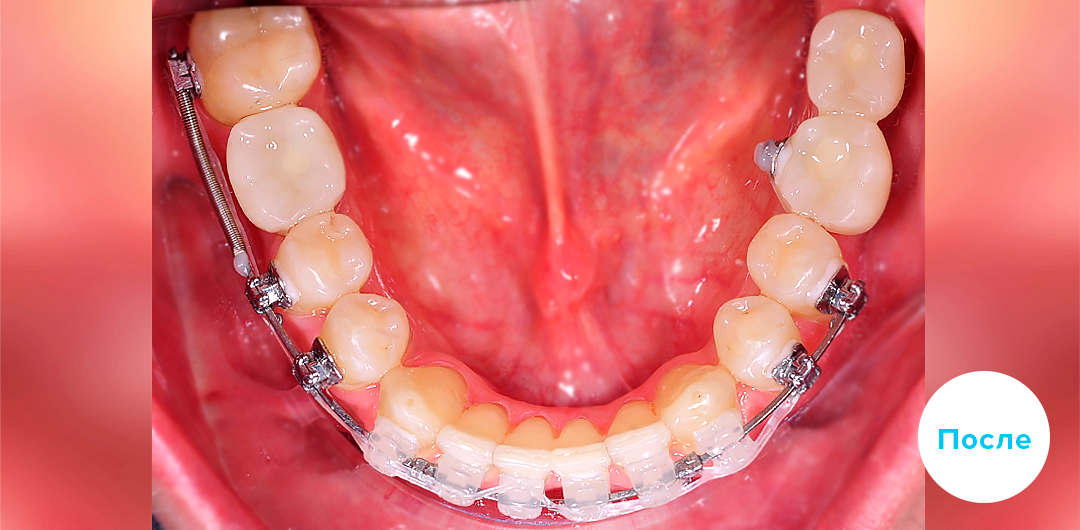

Ортодонтический аппарат Марко-Росса

Ортодонтический аппарат Марко-Росса

В приведенном клиническом случае ортодонты использовали индивидуальную цифровую брекет-систему INSIGNIA на базе керамических брекетов Damon Clear

Клинический случай

Подробнее о лечении:

Пациенту 39 лет. Выполнено удаление по терапевтическим показаниям зубов 4.6, 3.7 и 3.8 Имплантация проведена через 1.5 года после начала ортодонтического лечения. Параллельно проводилось закрытие промежутков на верхней челюсти задними зубами путем перемещения к мини-имплантатам Ортодонтическое лечение проводилось индивидуальной цифровой брекет-системой INSIGNIA (Инсигния), на базе керамических брекетов Damon Clear на обеих челюстях.